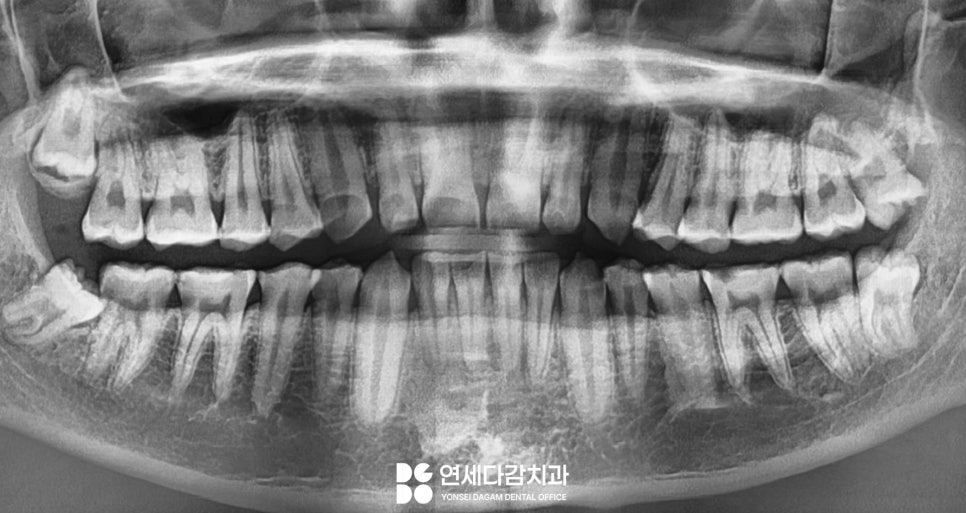

해당 사진을 보면 치아가

닳아 있는 형태를 띠고 있습니다.

그뿐만 아니라 심하면 마모를 넘어서

이렇게 치경부에

굴곡 파절이 생기기도 합니다.

해당 케이스는

평소 탄산음료를 즐겨 먹고,

역류성 식도염과

수면 중 이갈이 습관을 가졌을 때

나타난 구강 모습입니다.

문정동 치과 에서 보여드리는

케이스도 낮아진 모습을 보이고 있는데요.